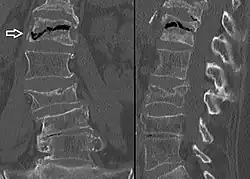

Compression fractures are usually diagnosed on spinal radiographs, where a wedge-shaped vertebra may be visible or there may be loss of height of the vertebra. In addition, bone density measurement may be performed to evaluate for osteoporosis. When a tumor is suspected as the underlying cause, or the fracture was caused by severe trauma, CT or MRI scans may be performed.

Compression fracture of the fourth lumbar vertebra post falling from a height. -